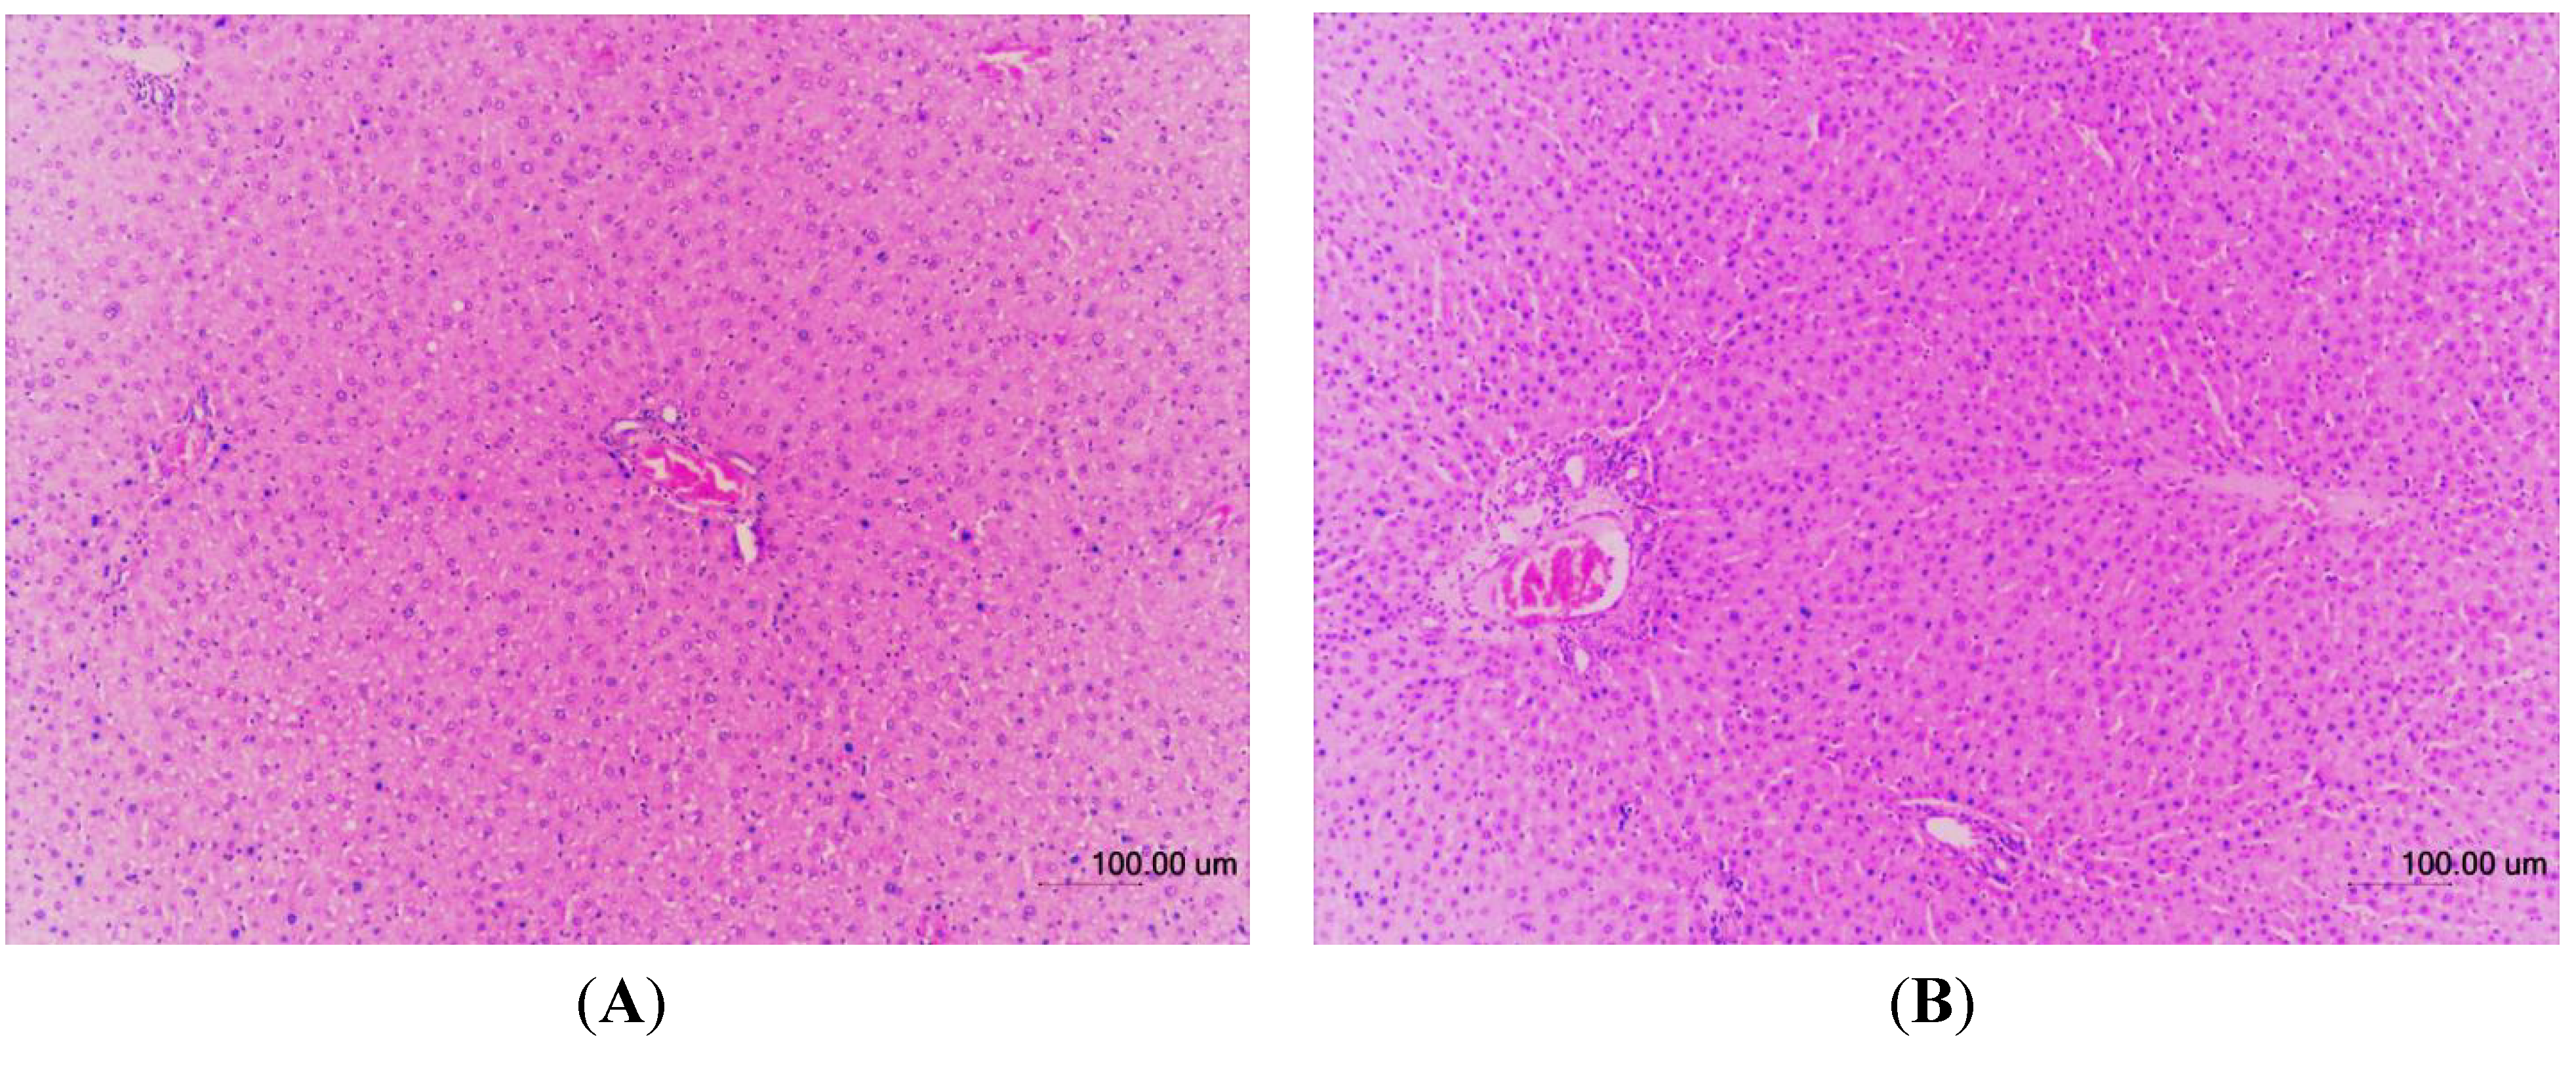

The histopathological examinations of the liver tissues from male and female rats were performed to further confirm whether or not the tissues had been damaged (Figure 3, Figure 4, respectively). No significant histopathological changes in the liver tissues of the experimental animals were observed. Compared to control groups all TQRFNE groups showed normal hepatic architecture with portal triad surrounded by the hepatocytes. Narrow sinusoids open freely into the portal vein. Gross and histopathological examinations further confirmed that the administration of TQRFNE (20 mL/kg) for both sexes of Sprague Dawley rats did not cause any evidence of liver tissue damage as compared to control groups. Therefore, the results suggest that the administration of 20 mL TQRFNE /kg is not toxic after an acute exposure.

Figure 3. Hematoxylin and Eosin-stained sections of male liver tissues from control (A) and TQRFNE (B) treated groups. No significant damage was detected in both groups.